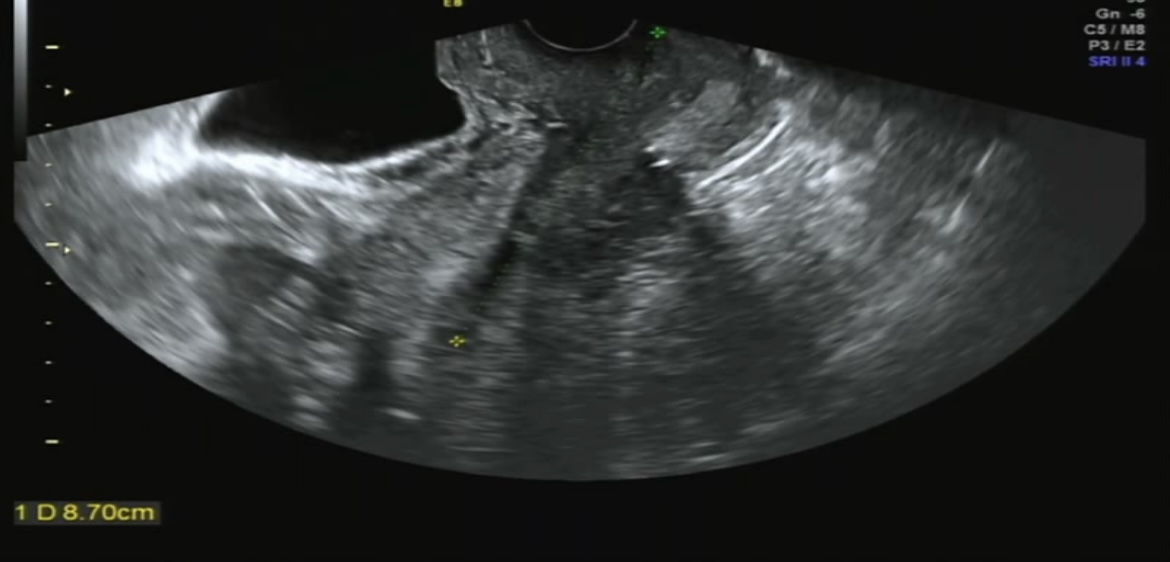

그리고 경부 길이 한번 재봤는데-

???????

8.7cm????

길이 재는 방식이 다른건가??

이게 가능한 길인가요..?

ㅎㅎ

길다고 하니 한결 안심되긴 했지만

뭔가 의심스러운 수치였다..